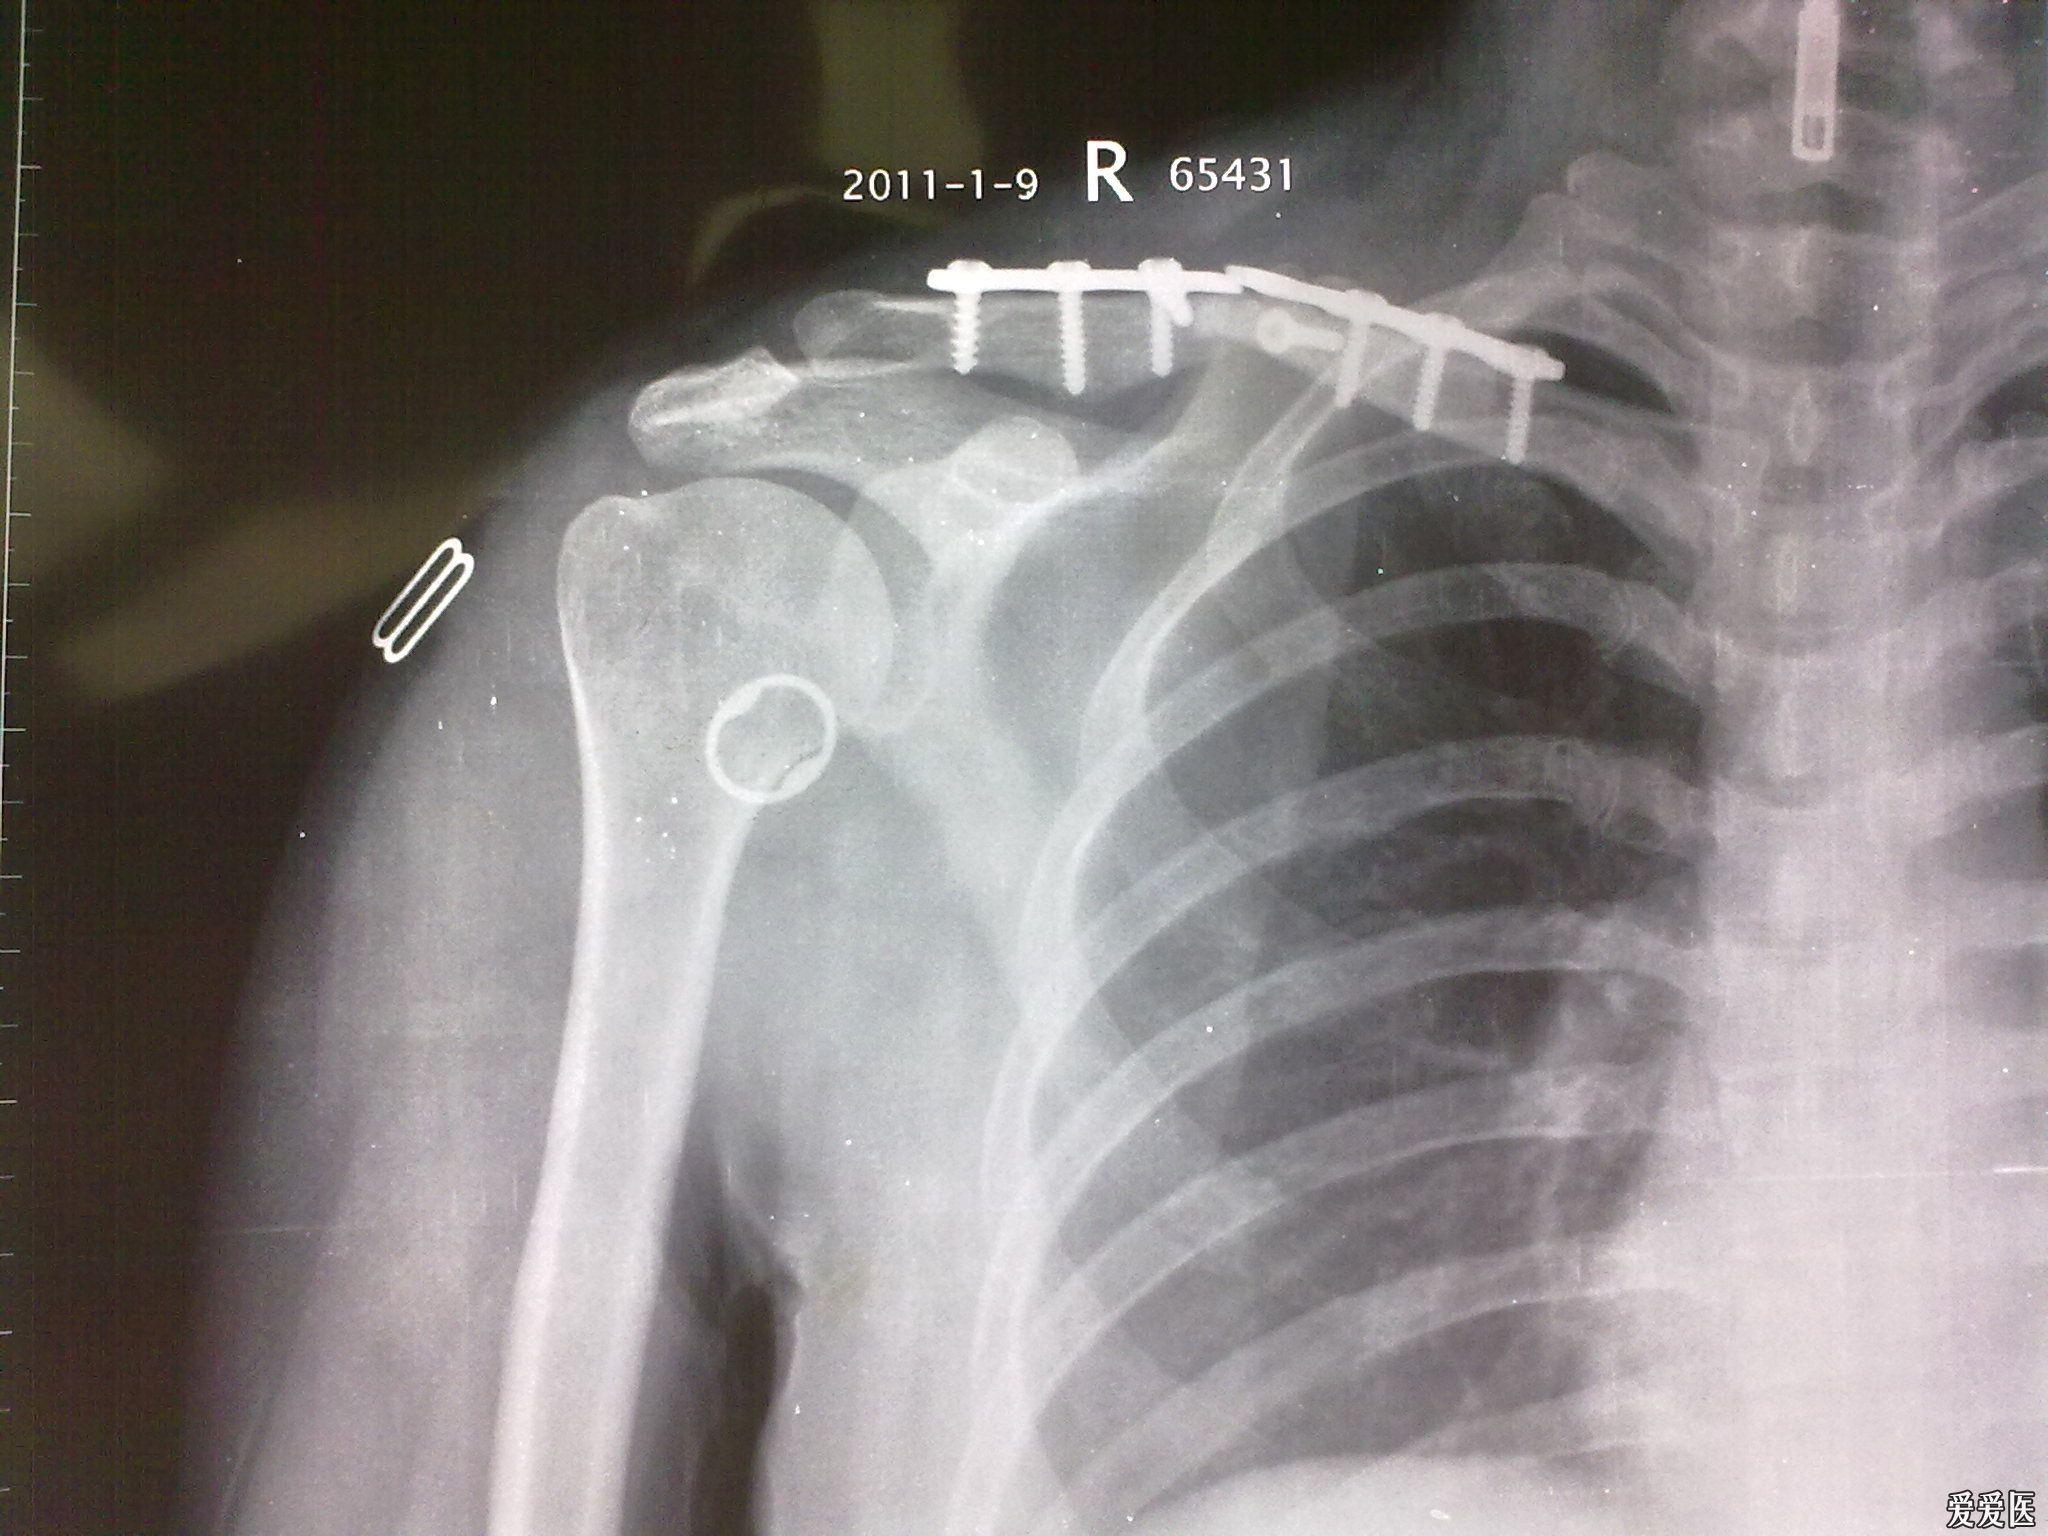

右锁骨骨折内固定术后19月内固定断裂

锁骨远端骨折,片子如图.求给意见,欢迎讨论.

锁骨肩峰端骨折_形体_医疗健康_医疗健康其他